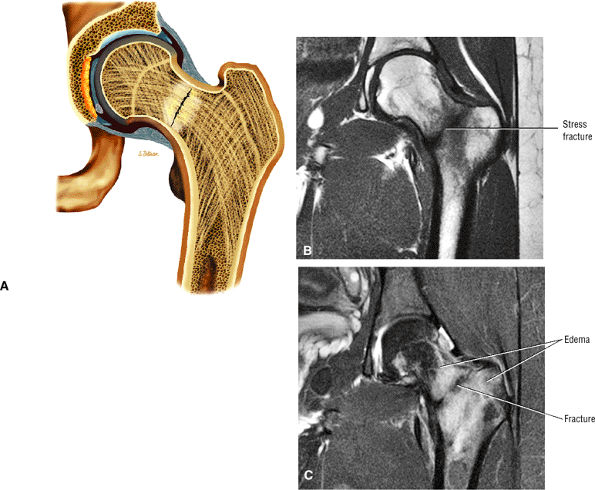

Most cases actually represent subchondral femoral head stress fractures, which can be appreciated on small-FOV images.

Normal appearance of articular cartilage, cortex, and subchondral bone

Diffuse or large areas of hypointensity within the femoral head and neck, sometimes extending to the intertrochanteric region and/or the acetabulum

A narrow line of sclerosis associated with a subchondral stress fracture

A homogeneous and well-marginated edema pattern

There may be marrow sparing in the medial and lateral-most margins of the femoral head and greater trochanter secondary to higher concentrations of fatty marrow.

Hyperintensity in the femoral head and neck, which is most conspicuous on FS PD or STIR images, sometimes accompanied by acetabular hyperintensity

A hypointense fracture line parallel to the subchondral plate (high-resolution imaging is necessary for visualization)

Marrow edema, which can be seen as early as 48 hours after the onset of clinical symptoms

Marrow sparing may be seen in the anterior, posterior, medial, or lateral aspect of the femoral head.

The edema interface is well defined without a demarcating hypointense line or band (no double-line sign).

The cortex and subchondral plate are normal, as are adjacent soft tissues.

There is a small to moderate hyperintense joint effusion.

FIGURE 3.98 ● A 40-year-old male patient with subtle subchondral stress fracture easily mistaken for transient osteoporosis. (A) Coronal T1-weighted image. (B) Coronal FS PD FSE image. (C) Sagittal FS PD FSE image.